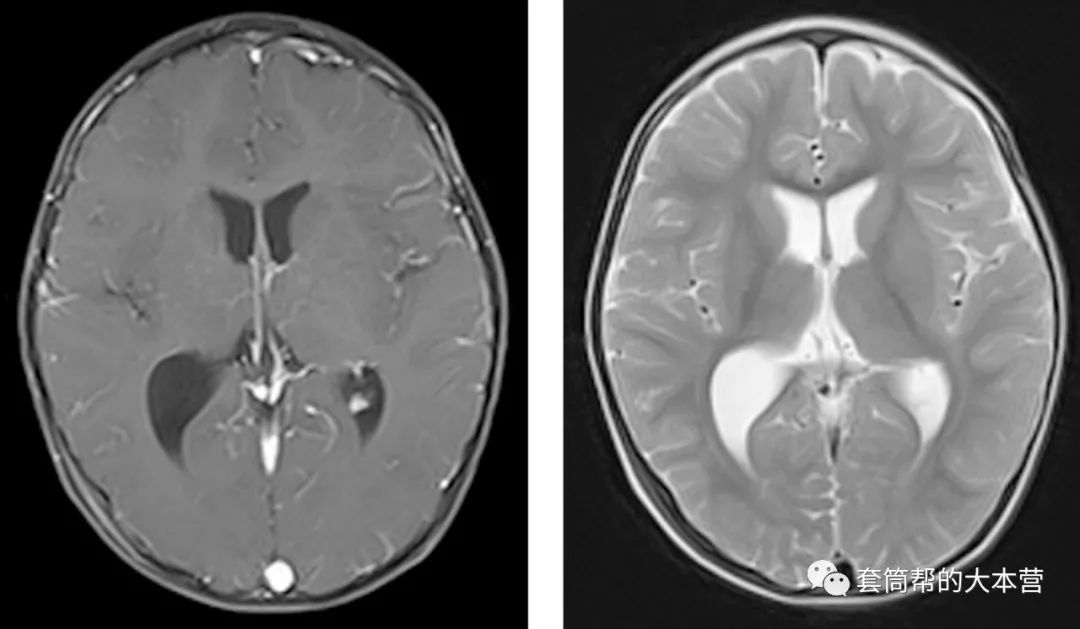

术后一个月,小宝宝回院复查。头颅磁共振证实了肿瘤全切除,而且手术的通道回弹很好,已经变得很窄,没有发生常规开颅手术时常见的脑穿通畸形。

术后1个月复查,肿瘤全切除